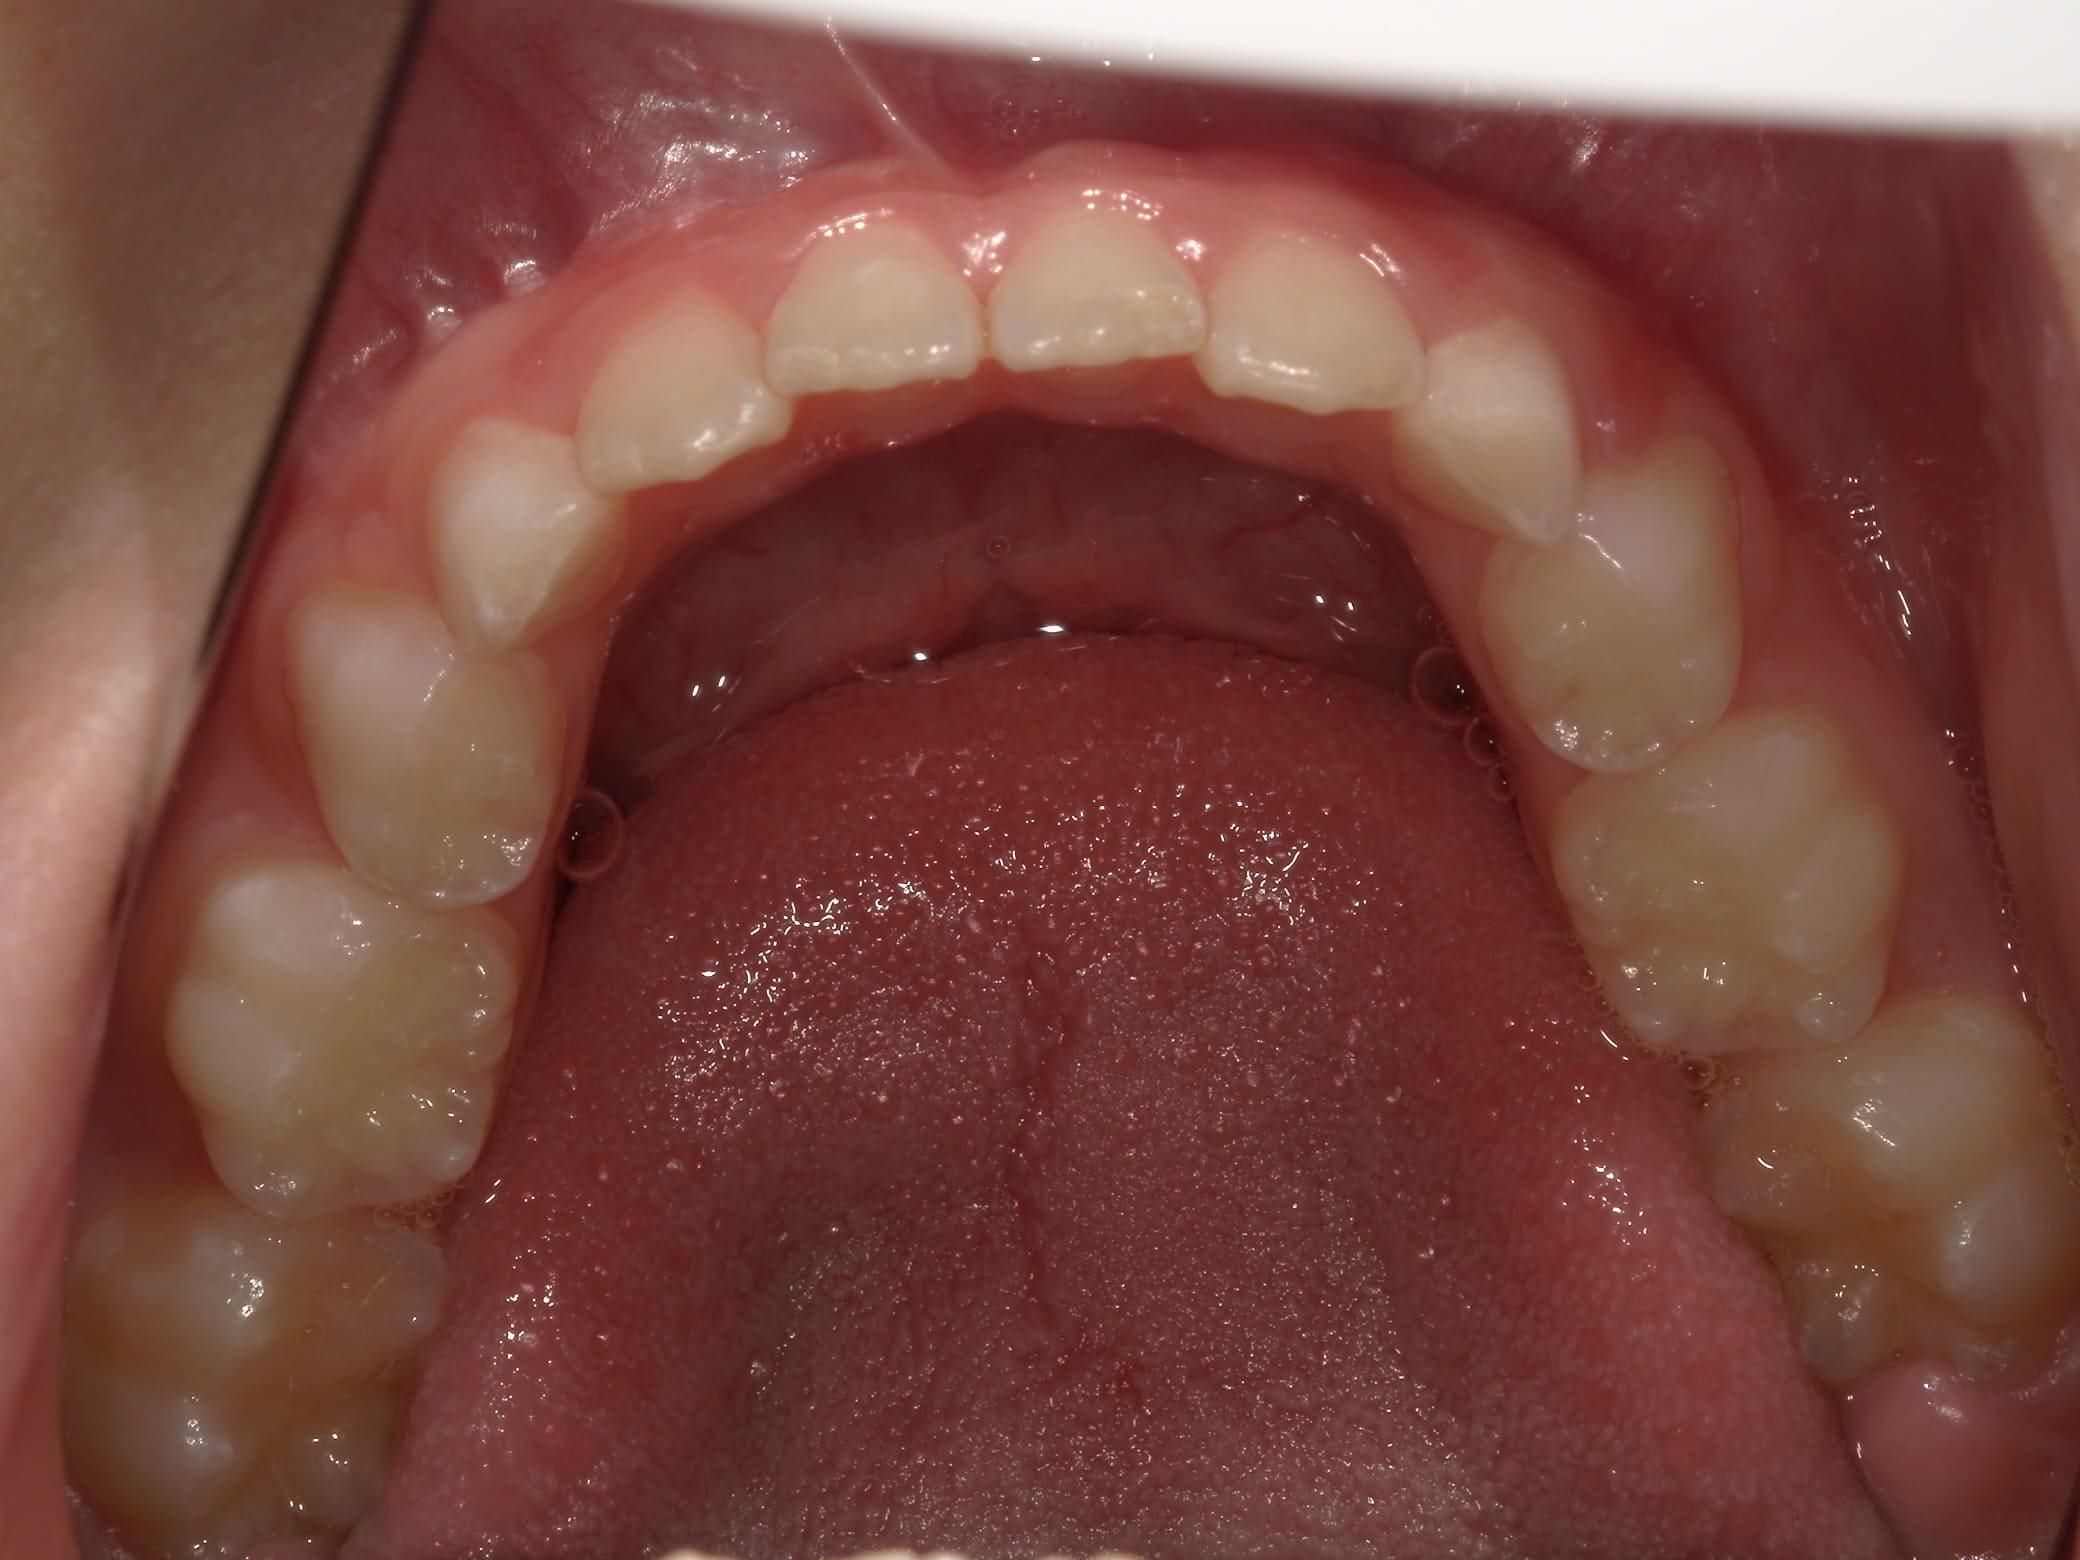

| 年齢・性別 | 7歳1ヶ月の男児 |

|---|---|

| 主訴 | 歯の生えるスペース不足が懸念され、歯列の乱れ(叢生)を整えるために来院された患者様です。 |

| 治療期間・回数 | 1年3ヶ月・11回 |

| 費用 | 420,000円(税別) |